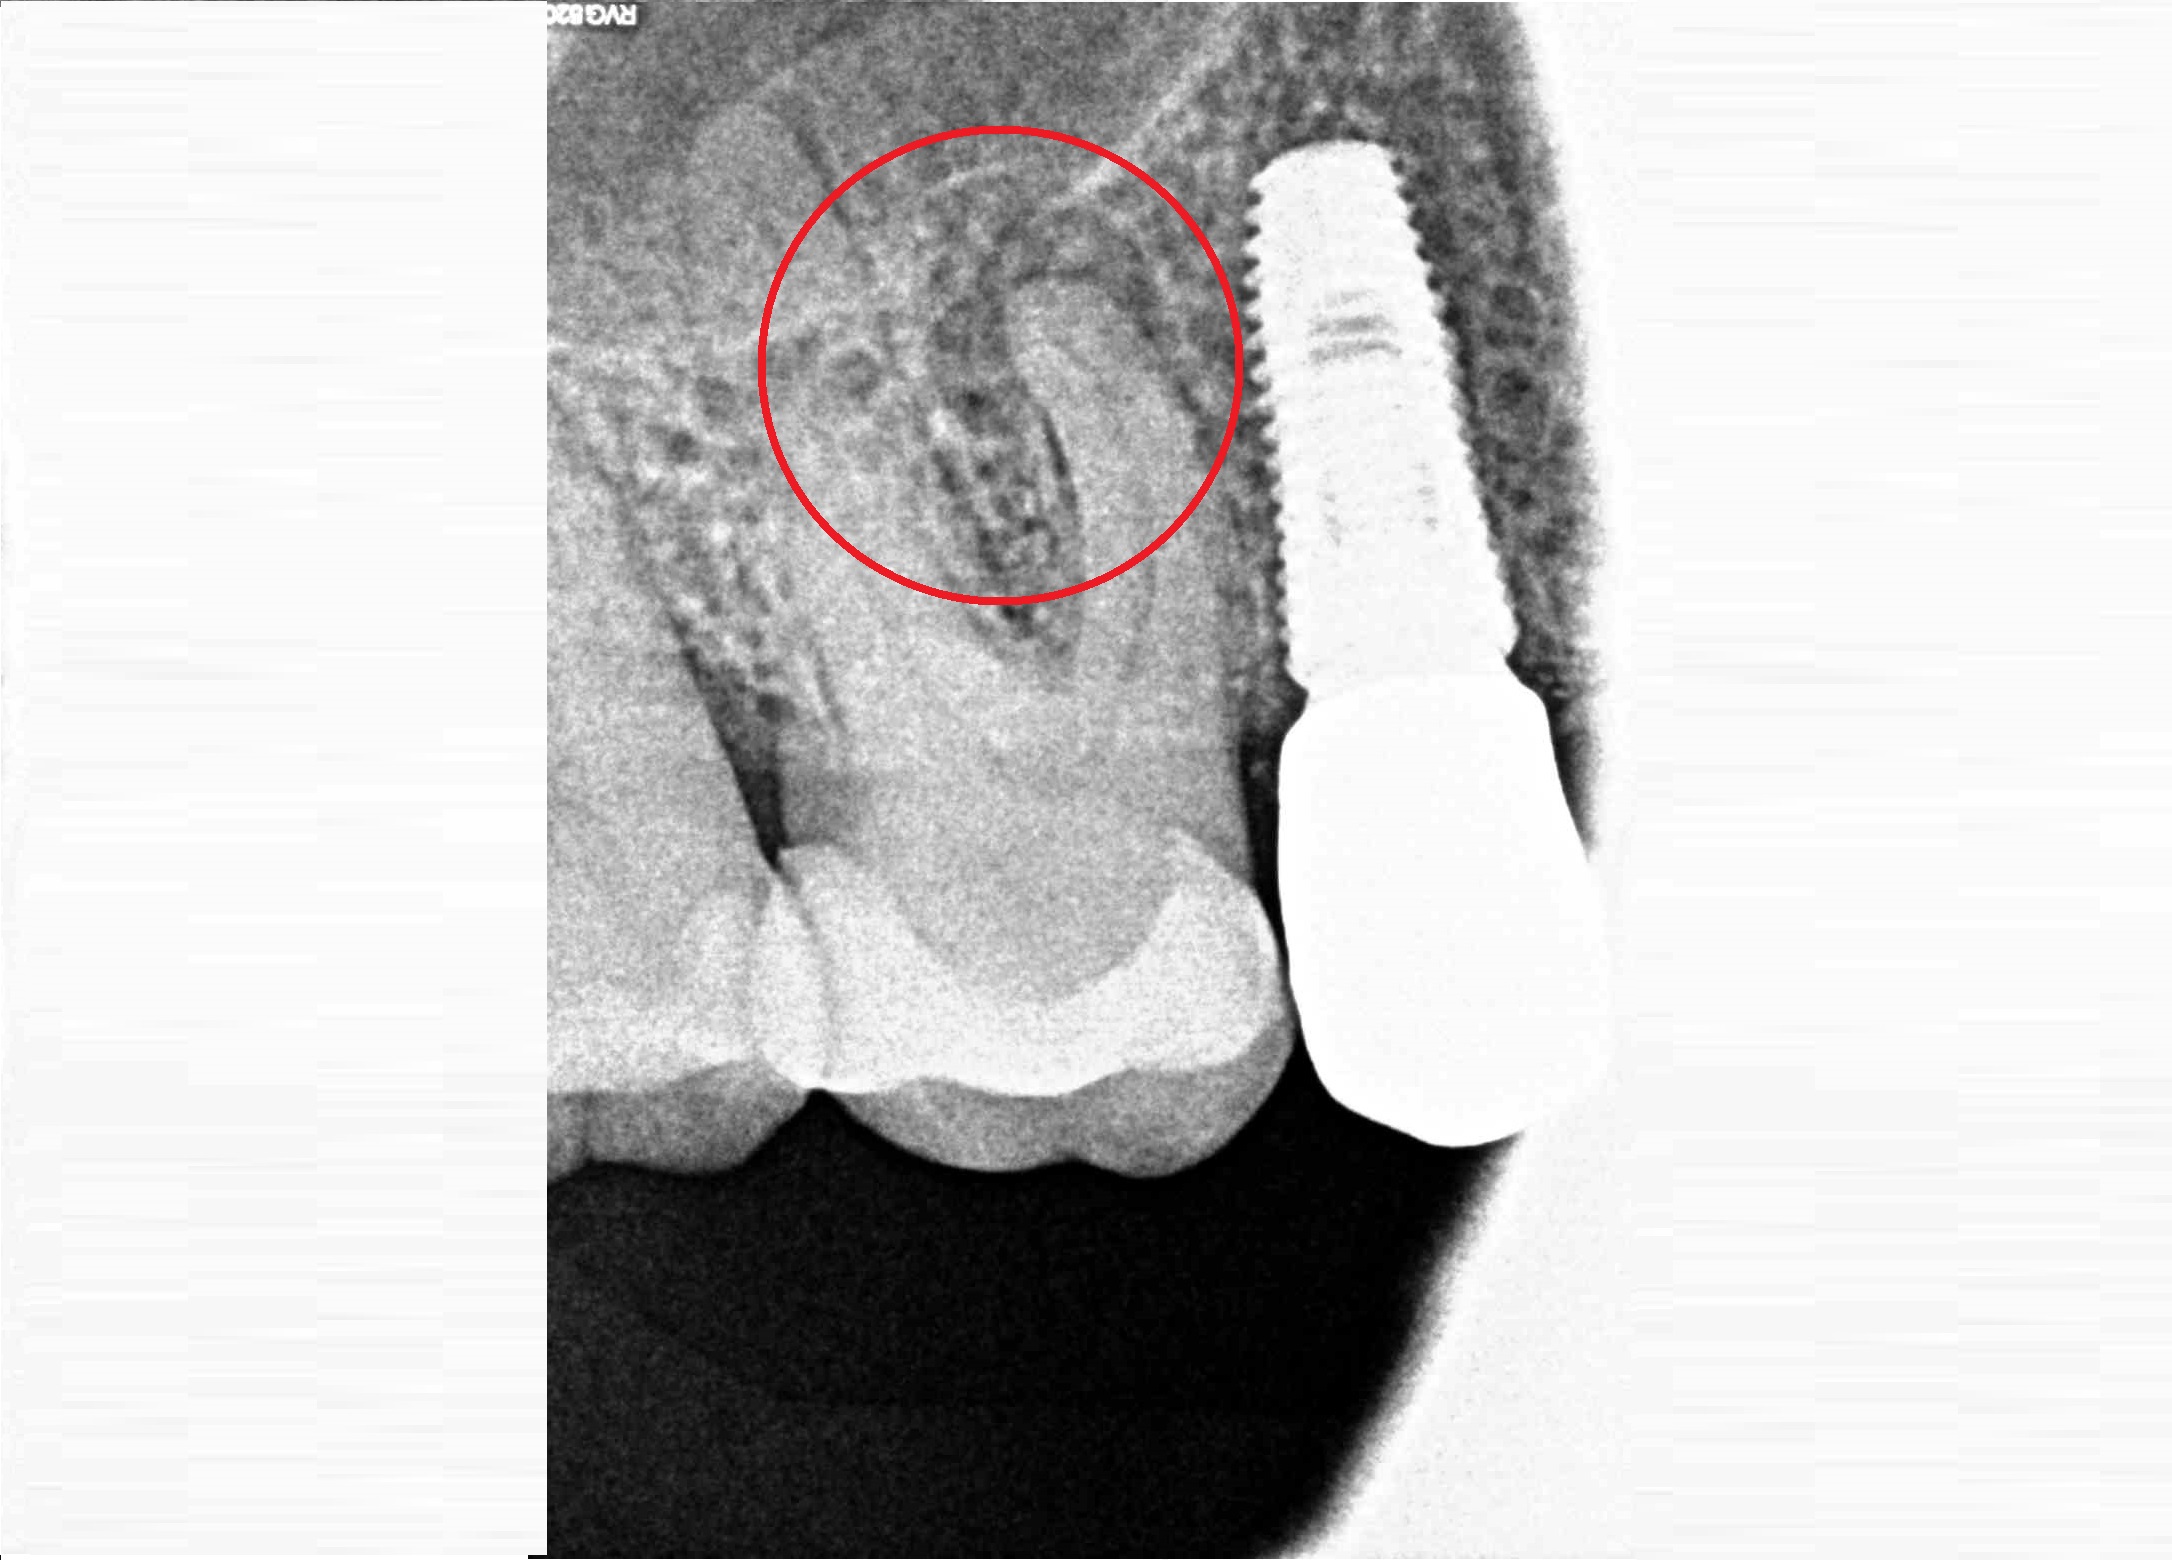

Проблема

Пациент обратился в клинику с проблемой отсутствия переднего зуба в следствии полученной травмы.

Решение

Пациенту проведено комплексное лечение по поводу восстановления переднего зуба при помощи имплантата Super Line и цельнокерамической коронки.